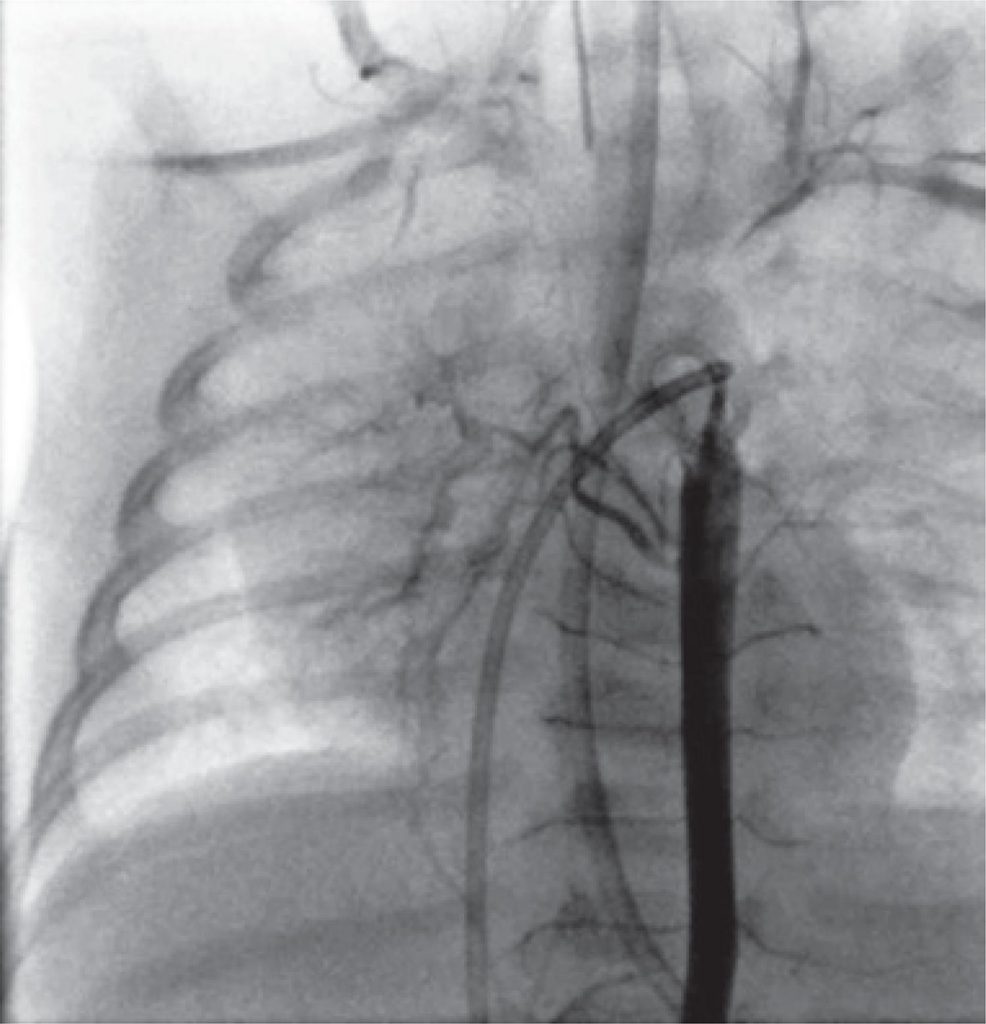

Na ecocardiografia transtorácica, o coração estava normal, em termos estruturais a funcionais. Porém, a artéria pulmonar direita não estava bem evidente. Foi realizada uma angiotomografia para esclarecer este achado, mas o resultado foi inconclusivo. Foram excluídos os diagnósticos de hemitruncus e persistência do canal arterial. Em seguida, foi submetido a cateterismo, e a angiografia pulmonar revelou agenesia da artéria pulmonar direita (), excluindo ramos ocultos da artéria pulmonar. O pulmão direito era perfundido pela árvore brônquica () e não foram encontradas outras anomalias.